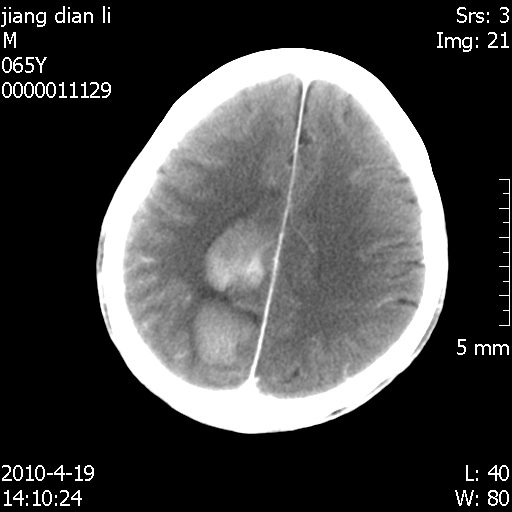

老年男性,突发左下肢无力1天,其余有价值的检查都没有。平扫ct值大约60hu,增强后ct值没什么改变,请大家讨论一下这个病例是什么?说明诊断理由。

左小脑、右大脑顶叶多发圆形高密度病灶,其周环状低密度影。考虑多发脑出血。隔期观察。

至于是出血还是微小钙化所致的高密度无法考证,三个都出血也不是一点都不可能,同一种组织学类型的肿瘤受到同一个外来的因素影响后会表现出相同的病理变化。说实在的,我本身支持转移瘤的,就是想不通为什么不强化?我认为单纯脑出血的边缘不会那么光滑,并且那也不是出血的常见部位,多发也不常见。

刚刚复习了转移瘤的不典型ct征象,有4条,分享给大家:

1、高密度灶:多为瘤内有较多沙粒体钙化所致,而不是出血,ct值可高达95hu;

2、无强化;

3、无水肿;

4、无占位效应。